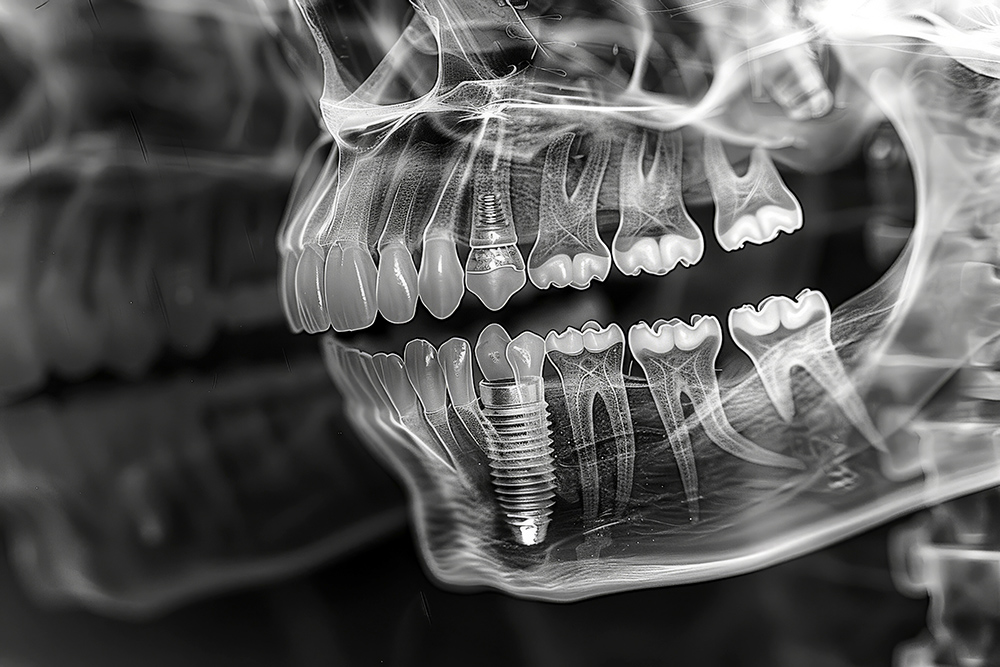

임플란트 시술 전, 의사는 환자와 초기 상담을 진행하며 환자의 요구사항과 건강 상태를 확인합니다. 이때 X-ray 촬영, 3D CT 스캔 등을 통해 환자의 구강 구조를 면밀히 분석합니다. 이 과정을 통해 시술 계획이 구체적으로 잡히며, 필요시 추가적인 치료(예: 뼈이식)가 논의될 수 있습니다.

본격적인 임플란트 식립 과정에서는 치조골에 인공치아 뿌리(임플란트)를 심습니다. 이 과정은 국소마취를 하며, 수술 시간은 보통 한 개당 30분에서 1시간 정도 걸립니다. 수술이 끝나면 잇몸을 봉합하고, 임플란트가 뼈에 완전히 결합될 때까지 기다려야 합니다.

임플란트가 뼈와 단단히 결합하는 과정을 '골유착'이라고 부릅니다. 이 기간은 약 3개월에서 6개월이 필요하며, 뼈 상태에 따라 다를 수 있습니다. 골유착이 잘 이루어져야만 임플란트가 안정적으로 자리잡고, 정상적인 기능을 수행할 수 있습니다.